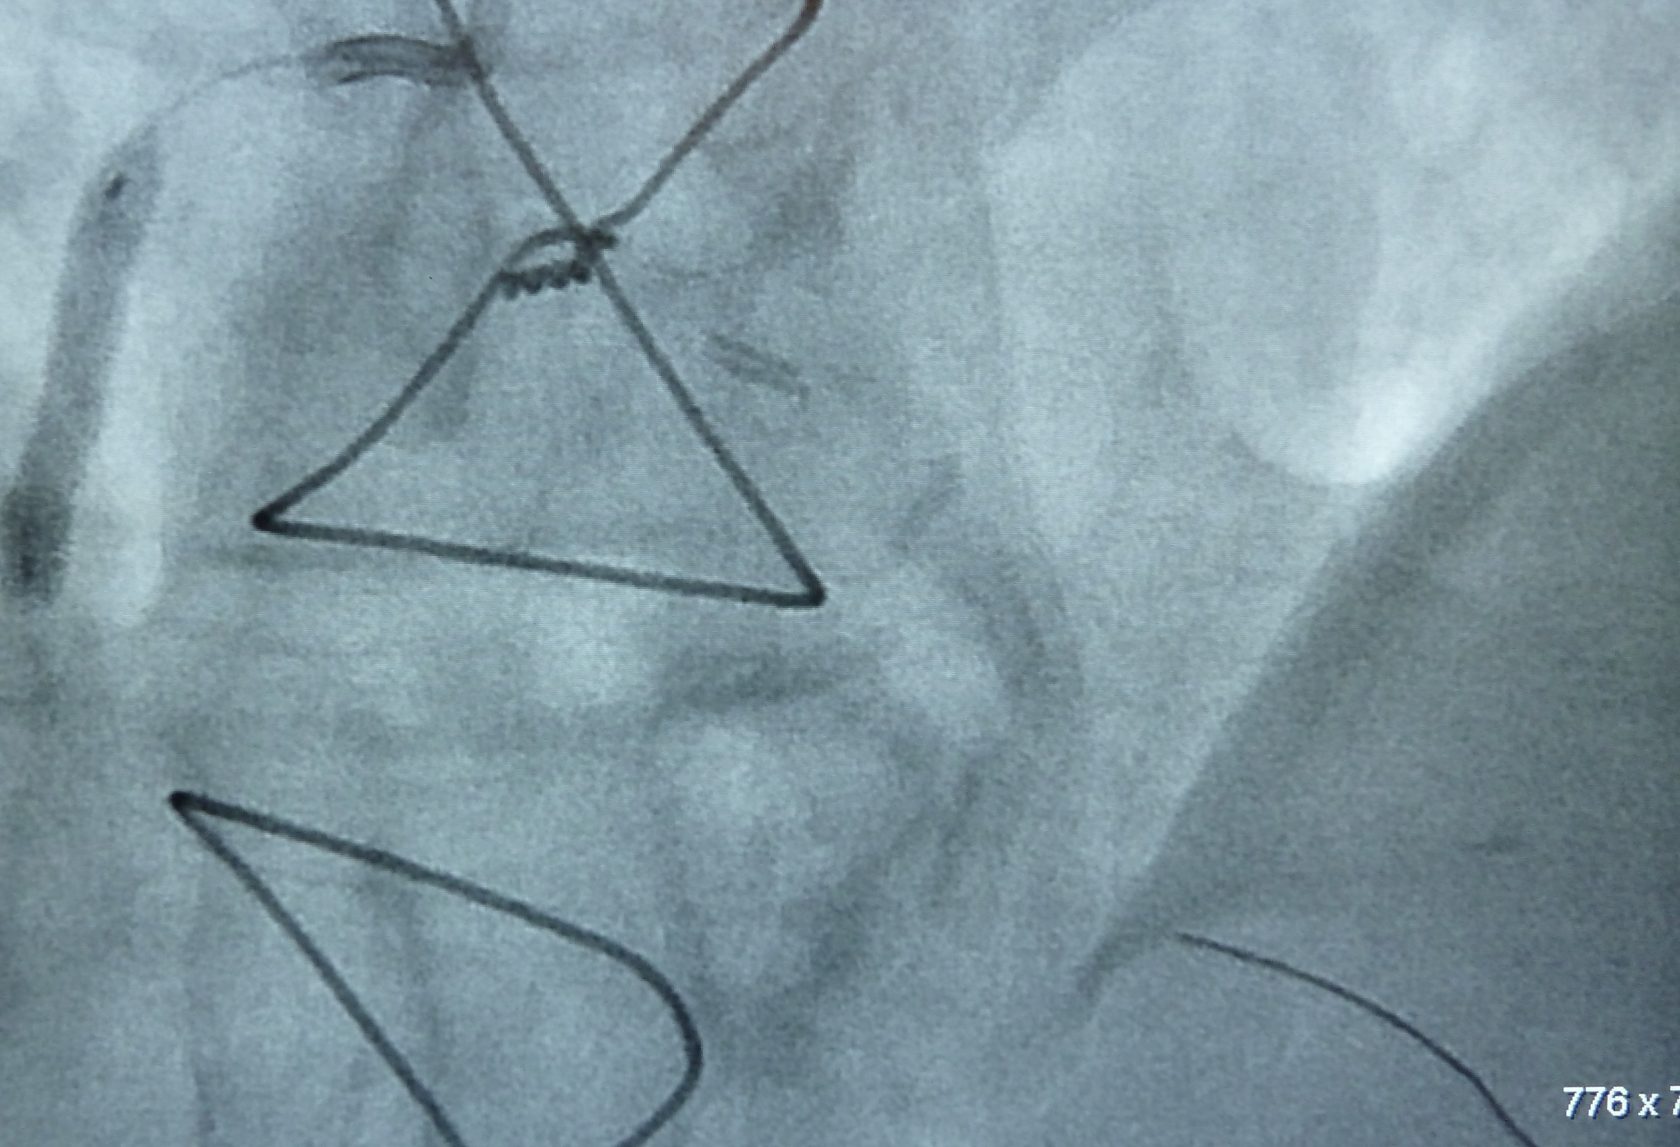

Die Stentimplantation ist ein Mittel zur Behandlung der Herzkranzgefäßerkrankung. Das Prinzip beruht darauf, dass eine Herzkranzgefäßverengung mittels Ballon aufgedehnt wird. Auflagerungen werden somit in die Gefäßwand gedrückt, wobei es zu einem Einreißen der Gefäßinnnenhaut kommen kann.

Der auf dem Ballon montierte Stent dehnt sich aus und hält das Gefäß in über 95% der Fälle dauerhaft offen. Damit wird die Durchblutung des Herzmuskels komplett wiederhergestellt.

Grundsätzlich ist das Vorgehen analog zur Herzkatheteruntersuchung. Vorbereitung und Einführung des Katheters geschehen wie dort geschildert. Es werden zunächst Medikamente zur Gerinnungshemmung und zur Erweiterung der Kranzarterien gespritzt. Durch den in der Kranzarterie liegenden Katheter wird nach Darstellung der Kranzarterie ein sehr weicher, flexibler Führungsdraht über die Kranzgefäßverengung vorgeführt. Über diesen als Leitschiene wird dann der eigentliche Ballonkatheter nachgeführt und der Ballon in der Verengung unter hohem Druck aufgeweitet. Sollte dies nicht gelingen, kann die Verengung auch mit einer speziellen Fräse abgetragen werden (Rotablation).

In den meisten Fällen ist auf dem Ballon direkt ein Stent (Gefäßstütze aus metallischem Maschenwerk) aufgesetzt, der durch die Dehnung in die Gefäßwand gepresst wird. Der Druck im Ballon wird entlastet und dieser entfernt. Der Stent bleibt lebenslang im Gefäß und wächst innerhalb Monaten ein. Nach Kontrolle durch Darstellung des Gefäßes wird der Katheter und die Schleuse entfernt.